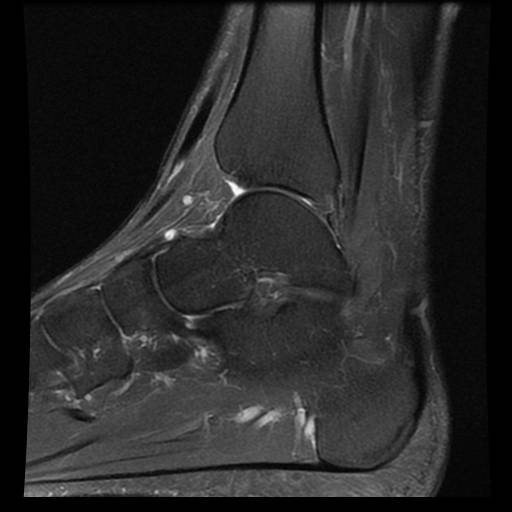

白色文字(排除指定关键词) Imaging Anatomy: interactive PACS-like atlas of radiological anatomy

解剖学模块